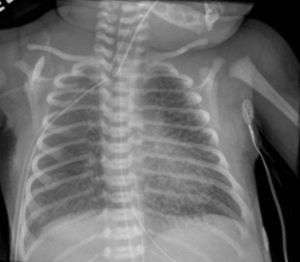

Pulmonary interstitial emphysema

| Chest radiography showing severe pulmonary interstitial emphysema | |

Pulmonary interstitial emphysema (PIE) is a collection of air outside of the normal air space of the pulmonary alveoli, found instead inside the connective tissue of the peribronchovascular sheaths, interlobular septa, and visceral pleura. (This supportive tissue is called the pulmonary interstitium.) This collection of air develops as a result of alveolar and terminal bronchiolar rupture. Pulmonary interstitial emphysema is more frequent in premature infants who require mechanical ventilation for severe lung disease. Infants suffering from pulmonary interstitial emphysema are typically recommended for admission to a neonatal intensive care unit.